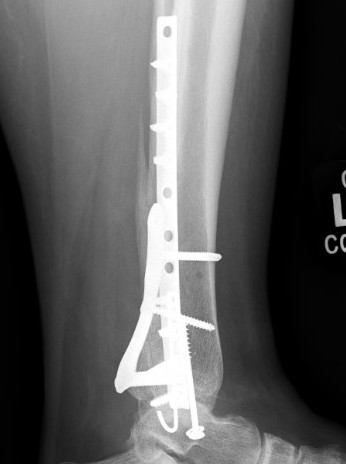

Tri-Malleolar Fracture

Lateral malleolus + medial malleolus + posterior malleolus

Posterolateral approach

- prone or lateral

- ORIF fibula + posterior malleolus

- move patient to supine to ORIF medial malleolus